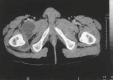

Musculoskeletal tuberculosis (TB) accounts for approximately 10% of all extrapulmonary TB cases in the United States and is the third most common site of extrapulmonary TB after pleural and lymphatic disease. Vertebral involvement (tuberculous spondylitis, or Pott's disease) is the most common type of skeletal TB, accounting for about half of all cases of musculoskeletal TB. The presentation of musculoskeletal TB may be insidious over a long period and the diagnosis may be elusive and delayed, as TB may not be the initial consideration in the differential diagnosis. Concomitant pulmonary involvement may not be present, thus confusing the diagnosis even further. Early diagnosis of bone and joint disease is important to minimize the risk of deformity and enhance outcome. The introduction of newer imaging modalities, including MRI (imaging procedure of choice) and CT, has enhanced the diagnostic evaluation of patients with musculoskeletal TB and for directed biopsies of affected areas of the musculoskeletal system. Obtaining appropriate specimens for culture and other diagnostic tests is essential to establish a definitive diagnosis and recover M. tuberculosis for susceptibility testing. A total of 6 to 9 months of a rifampin-based regimen, like treatment of pulmonary TB, is recommended for the treatment of drug susceptible musculoskeletal disease. Randomized trials of tuberculous spondylitis have demonstrated that such regimens are efficacious. These data and those from the treatment of pulmonary TB have been extrapolated to form the basis of treatment regimen recommendations for other forms of musculoskeletal TB.